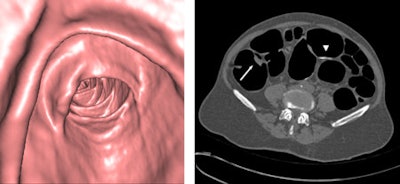

Images were interpreted by one of two experienced radiologists on a workstation (Wizard with syngo colonography software, Siemens) using a primary 3D interpretation technique with 2D problem-solving. Fiber-optic colonography was performed on patients with CTC-detected polyps or masses within 92 days following a positive CTC exam. Lesion measurement was performed using a visual comparison and used for polyp matching with the CTC results.